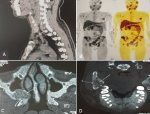

Brown tumours are rare bone manifestations of primary or tertiary hyperparathyroidism, secondary to osteoclastic resorption, that can mimic tumours or metastatic lesions and compromise functional and aesthetic outcomes. We report two cases illustrating their topographic and radiological diversity. A 34-year-old man, followed for recurrent nephrolithiasis, presented with a swelling of the right wrist. Laboratory investigations revealed hypercalcemia at 153 mg/L, parathyroid hormone (PTH) levels 27 times the upper limit of normal, hypophosphatemia, and hypercalciuria, confirming primary hyperparathyroidism with bilateral parathyroid adenomas and multiple diffuse osteolytic lesions on 18F-choline PET (A, B). A 30-year-old woman on hemodialysis presented with diffuse bone pain and maxillomandibular swellings, appearing as lytic lesions on craniofacial CT scan (C, D). A PTH level of 3,498 pg/mL, together with identification of a parathyroid nodule on MIBI scintigraphy, confirmed the diagnosis of tertiary hyperparathyroidism. Both patients underwent bone biopsy revealing giant cells and parathyroidectomy followed by vitamin D and calcium supplementation, resulting in clinical, biological, and morphological improvement. Early recognition of brown tumors is essential to prevent severe skeletal complications and to guide appropriate management.

Les tumeurs brunes sont des manifestations osseuses rares de l'hyperparathyroïdie, primaire ou tertiaire, secondaires à une résorption ostéoclastique, pouvant simuler des lésions tumorales ou métastatiques et compromettre le pronostic fonctionnel et esthétique. Nous rapportons deux observations illustrant leur diversité topographique et radiologique. Un homme de 34 ans, suivi pour lithiases rénales récidivantes, présentait une tuméfaction au poignet droit. Au bilan: hypercalcémie à 153 mg/l, PTH x 27 la normale, hypophosphorémie et hypercalciurie confirmant l'hyperparathyroïdie primaire avec présence d'adénomes parathyroïdiens bilatéraux et de multiples lésions ostéolytiques diffuses à la PET 18F-choline (A, B). Une femme hémodialysée de 30 ans avait des douleurs osseuses diffuses et tuméfactions maxillo-mandibulaires se présentant par des lésions lytiques à la TDM crânio-faciale (C, D). La PTH à 3498 pg/ml avec individualisation d'un nodule parathyroïdien à la scintigraphie MIBI ont confirmé l'hyperparathyroïdie tertiaire. Les deux patients ont bénéficié de biopsie osseuse révélant des cellules géantes et d'une parathyroïdectomie avec supplémentation vitamino-calcique, aboutissant à une amélioration clinico-biologique et morphologique. La reconnaissance précoce des tumeurs brunes est essentielle pour prévenir les complications osseuses sévères et orienter la prise en charge.

Figure 1: A) adénome parathyroïdien inférieur à la PET 18F-choline; B) tumeurs brunes diffuses (lésions ostéolytiques avec hyperfixation du radiotraceur) à la PET 18F-choline; C) tumeur brune maxillaire droite sur TDM crânio-faciale; D) tumeur brune mandibulaire droite sur TDM crânio-faciale